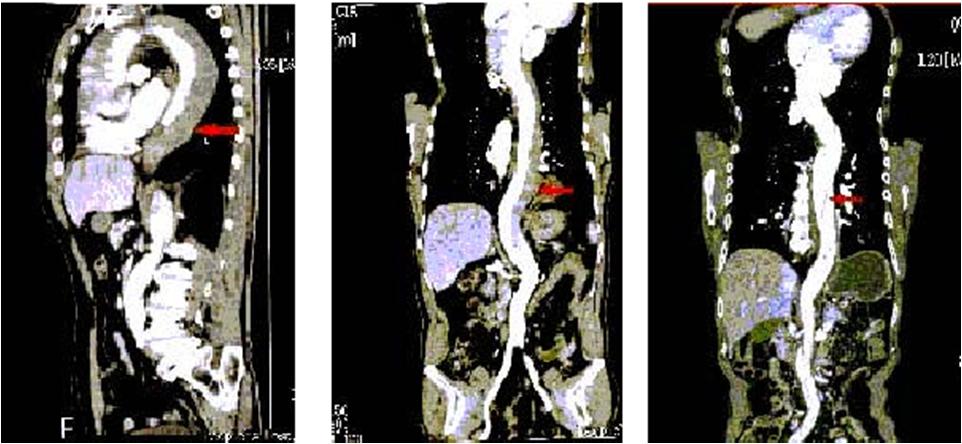

在MPR, CPR图象中,主动脉夹层的真假腔显示不同密度,真腔明显强化,真腔小而假腔大,真腔明显受压变窄,可见低密度血栓。

(3)主动脉夹层的X-线胸片: 增宽的纵隔和左侧腔积液: